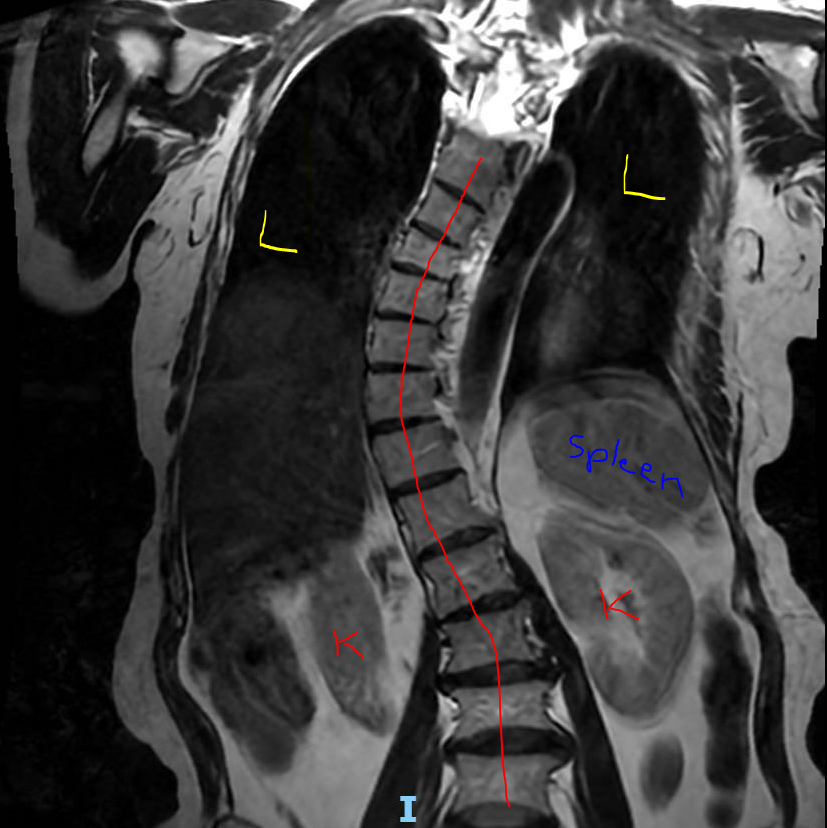

I traced the vertebral column in red 🔴, and you can clearly see an S-shaped curve. When viewed in the coronal plane, this lateral deviation is called scoliosis. In more pronounced cases, surgical correction may be needed to straighten the spine and relieve symptoms such as back…

whitfieldlewis6's tweet image. I traced the vertebral column in red 🔴, and you can clearly see an S-shaped curve. When viewed in the coronal plane, this lateral deviation is called scoliosis. In more pronounced cases, surgical correction may be needed to straighten the spine and relieve symptoms such as back…